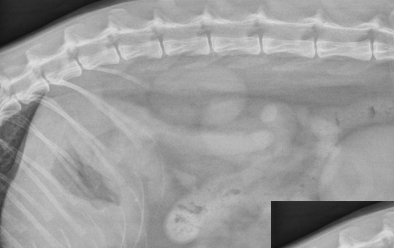

what is going on here bruh??

there is a mineralized adrenal mass. on the VD the mass is seen just left to the spine, and on the lateral, you can see a crescent shape opacity adjacent to the left kidney.